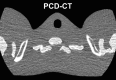

Photon-counting detector (PCD) CT is an emerging technology that has shown tremendous progress in the last decade. Various types of PCD CT systems have been developed to investigate the benefits of this technology, which include reduced electronic noise, increased contrast-to-noise ratio with iodinated contrast material and radiation dose efficiency, reduced beam-hardening and metal artifacts, extremely high spatial resolution (33 line pairs per centimeter), simultaneous multienergy data acquisition, and the ability to image with and differentiate among multiple CT contrast agents. PCD technology is described and compared with conventional CT detector technology. With the use of a whole-body research PCD CT system as an example, PCD technology and its use for in vivo high-spatial-resolution multienergy CT imaging is discussed. The potential clinical applications, diagnostic benefits, and challenges associated with this technology are then discussed, and examples with phantom, animal, and patient studies are provided. ©RSNA, 2019.